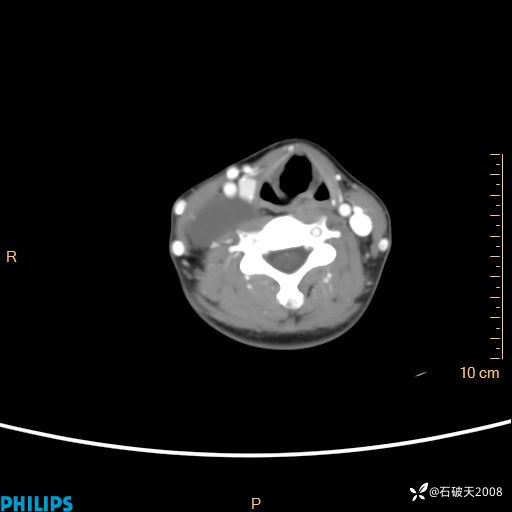

影像诊断要密切结合临床,真的很有必要(病理已公布)

女 21岁 主 诉:发现右侧颈部肿物18年余。

现病史:18年余前患者无明显诱因发现颈部偏右侧有一肿物,具体大小不明确,咳嗽、憋气时肿物增大,局部无疼痛,无吞咽不适,无胸闷及呼吸困难,至当地医院检查考虑良性病变(具体不详)并未做特殊处理,现患者自觉肿物随年龄增长而进一步变大,今日至我院行颈部CT平扫+增强提示:1.右侧颈根部、锁骨上窝及纵隔内异常密度影,考虑良性病变,淋巴管瘤?囊肿?请结合临床。2.双侧颈部小淋巴结。建议结合临床及其他相关检查。现为行进一步治疗,门诊以“颈部局部肿物”为诊断收住我科,发病来患者神志清,精神可,饮食睡眠可,大小便正常,体重无下降。

动脉期